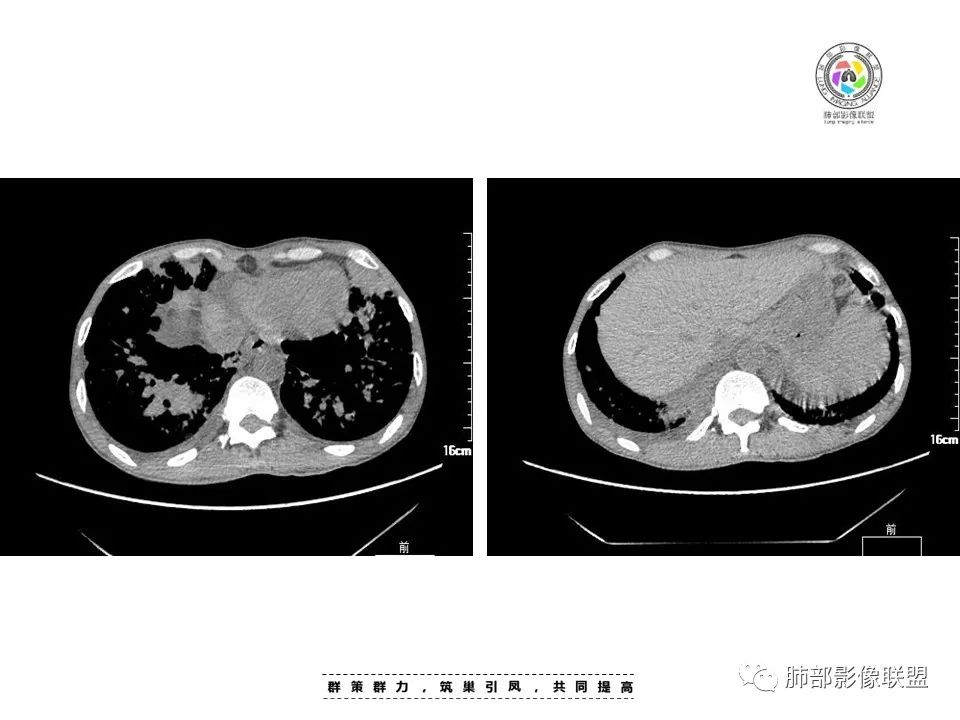

2022.8.29晚读:病例1

男,45岁

病史:发热、纳差、乏力、皮疹1月。T38.4℃,,全身散在暗紫色丘疹。CD8高,CD4低。CA-125略高。

两肺弥漫性性结节状、小片状及片状带晕的病灶,煎蛋征、点晕征,主要分布两肺中下叶,病灶周围小叶间隔增厚呈网格状影,部分病灶累及胸膜,伴两侧胸膜增厚。

印象:

真菌性肺炎,弥漫性病变,形态多样,混合晕征。

病毒性肺部感染,表现为肺部晕征及点晕改变。

血管炎:病灶累及下血管,肺泡及腺泡填充,周围渗出,代表出血,并累及气道。ANCA相关性的血管炎,包括GPA、MPA和EGPA,结合临床全身散在暗紫色丘疹,可以考虑。

肿瘤性病变:转移瘤?淋巴瘤?等

2.本例双肺小叶间隔增厚明显,多发结节影及片状实性密度影,沿血管支气管束分布为主,两侧较为对称,病灶多环以磨玻璃晕,边界不清。

双侧胸腔少量积液。双肺门及纵隔未见明确肿大淋巴结,纵隔结构间隙模糊。

3.有学者将这种具有沿双肺支气管束分布的实性密度片影描述为“火焰征”,认为具有一定特征性,单就影像表现而言,这种影像表现也可以见于其他病损或多种病理改变的叠加。